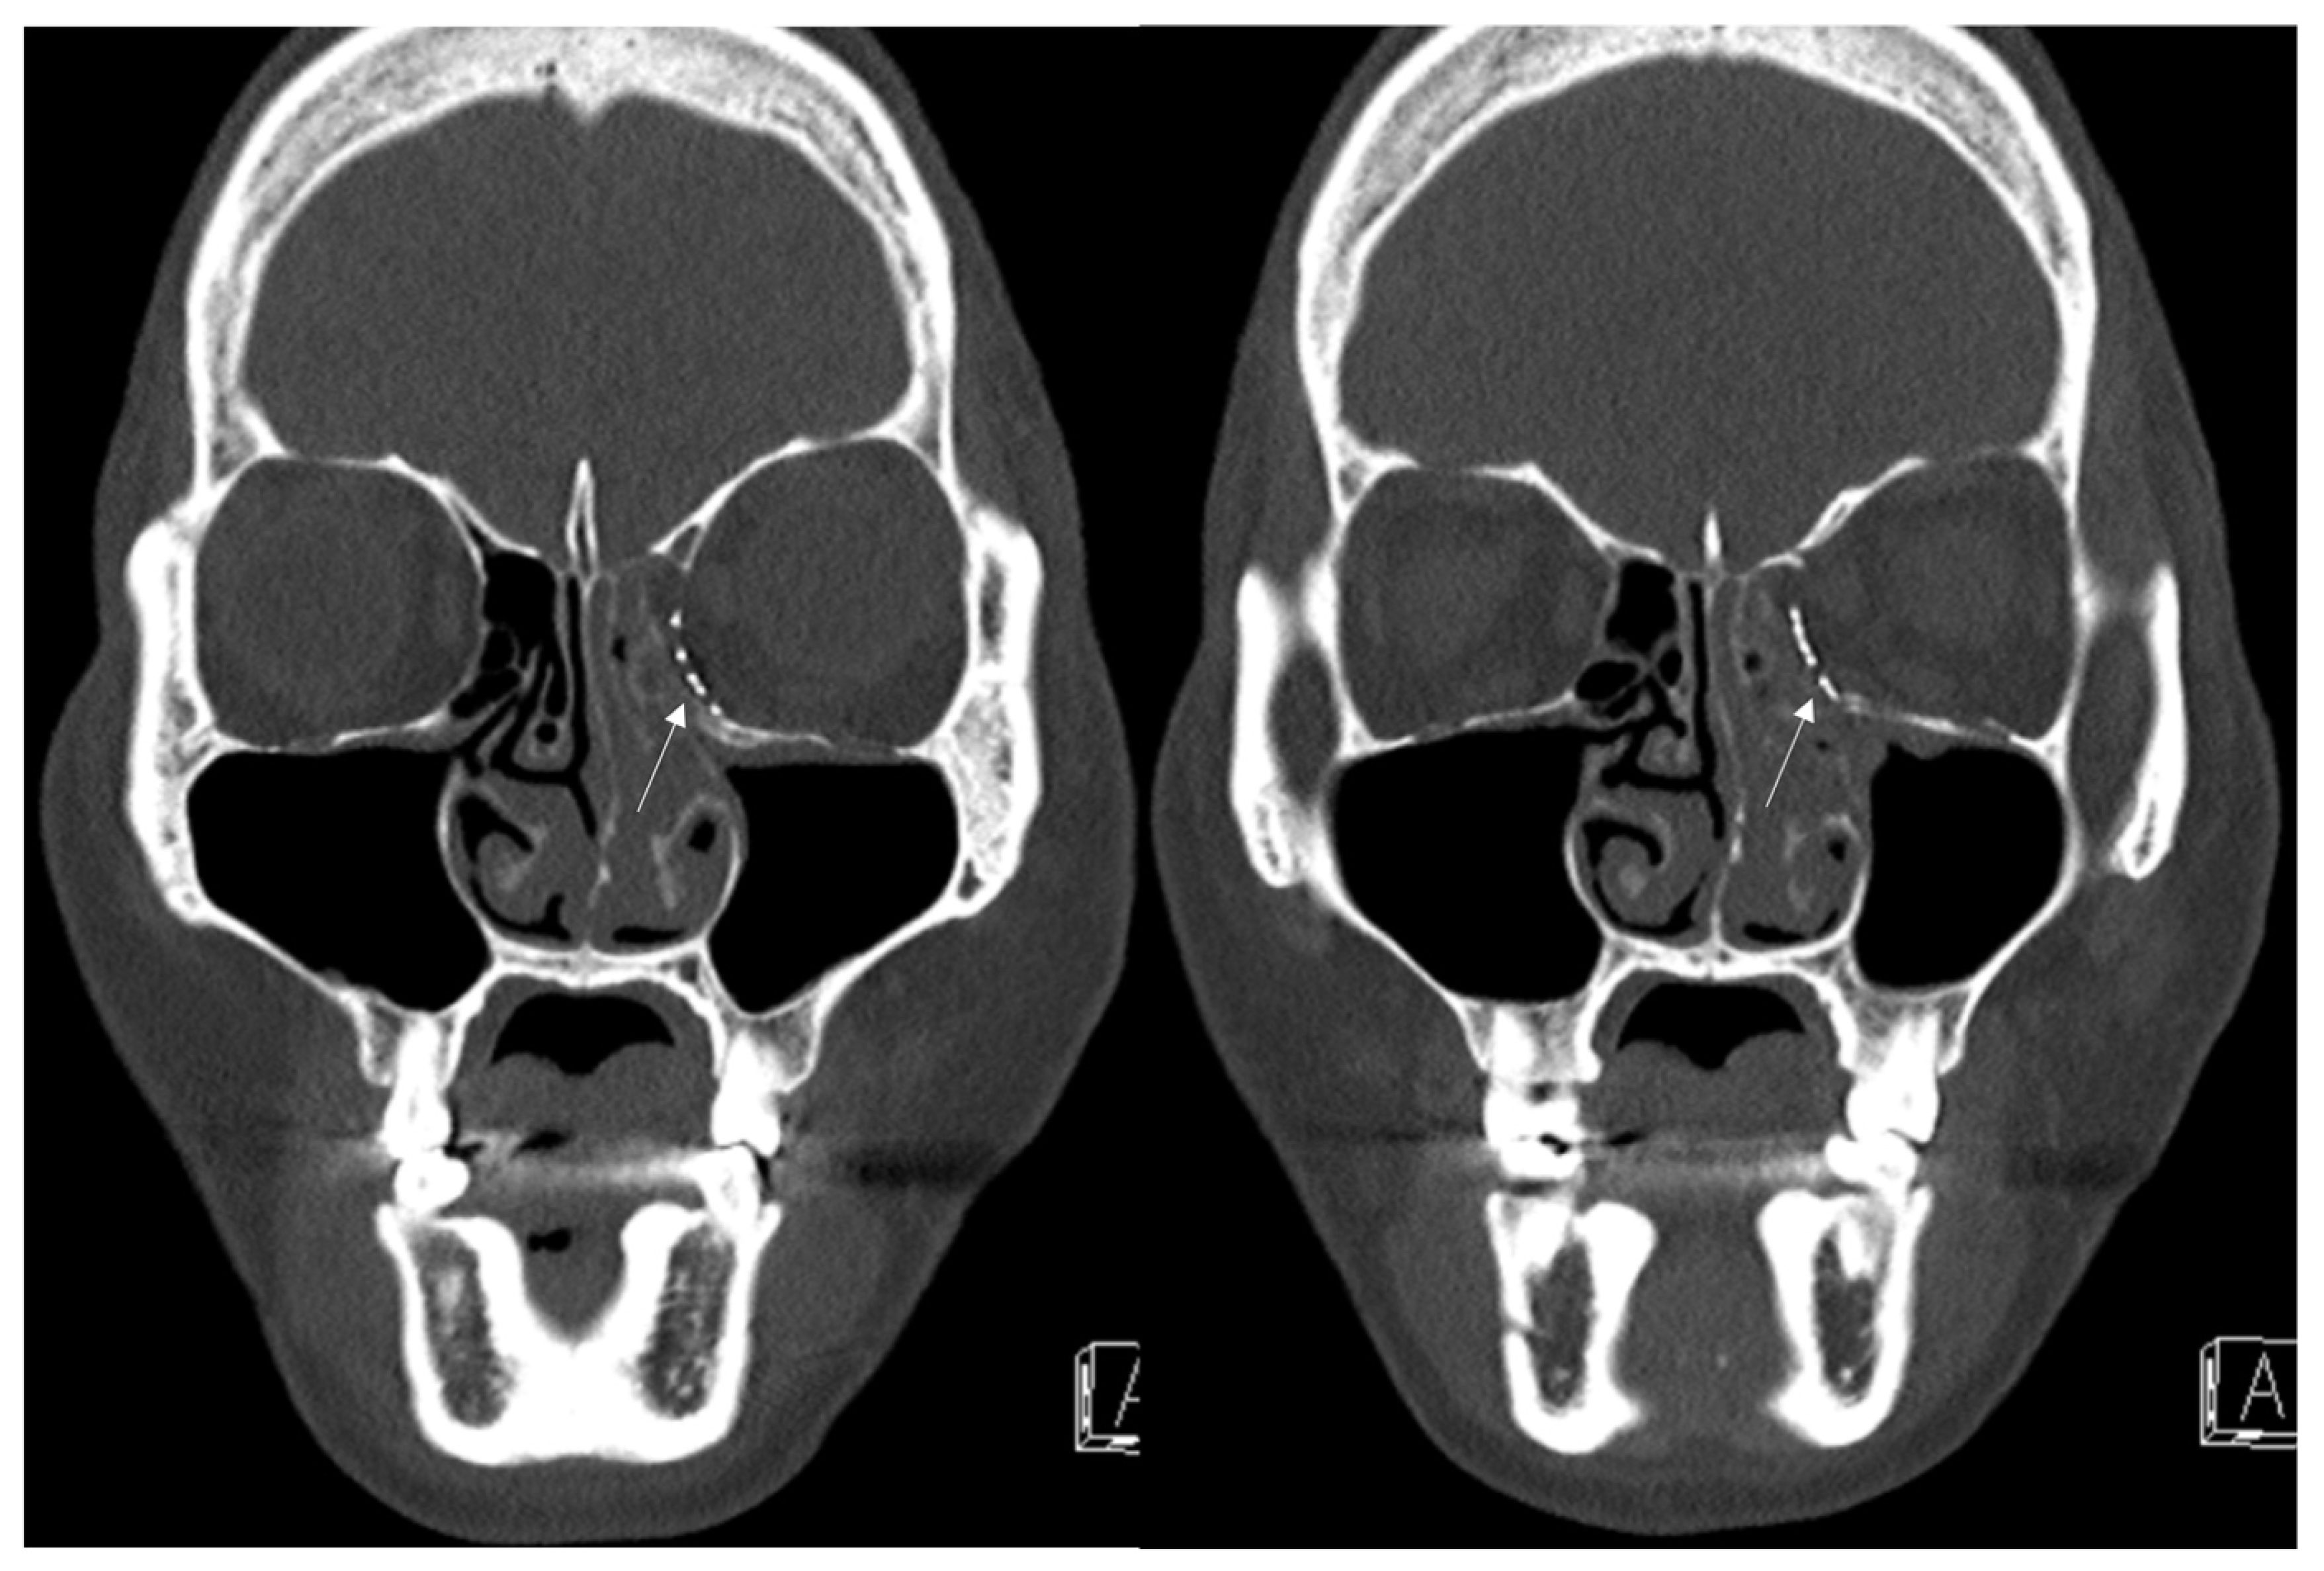

3.3. Case 3

A 34-year-old female patient came to our clinic with left eyeball swelling and ecchymosis caused by a direct trauma to the eyeball. The patient complained of pain and discomfort with eyeball movement (Figure 5). We surgically approached the medial orbital wall fracture two days after the accident. After the subciliary incision, the fracture was exposed. The titanium-reinforced porous polyethylene (TR-PPE) plate was placed on the fracture site using a single screw at the inferior orbital rim (Figure 6). The patient was discharged on postoperative day 2 with significantly improved pain and discomfort.

Figure 5. Case 3. Preoperative facial CT scan (coronal and axial view) of the 34-year-old female patient with left medial orbital wall fracture (white arrow). The fracture sites were designated with white arrows.

Figure 6. Case 3. Follow-up facial CT finding (coronal and axial view) of the same patient. The titanium-reinforced porous polyethylene (TR-PPE) plate was placed on the inferomedial orbital wall using a single screw at the inferior orbital rim. (White arrow).